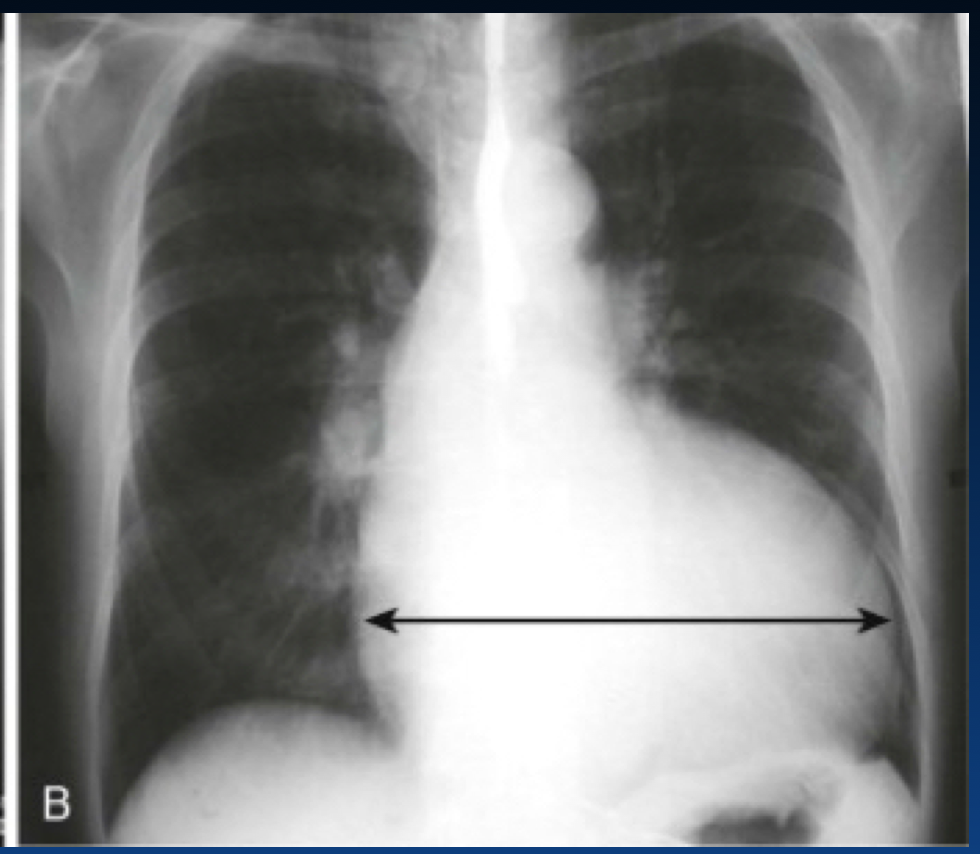

What are the reasons for increased CTR?

This does not show a real increase CTR. Why?

You can tell an expiration by the height of diaphragm as well as counting the ribs (the right only shows 4 ribs). You should see 6 or 7 ribs.

What is the Cardiothoracic Ratio?